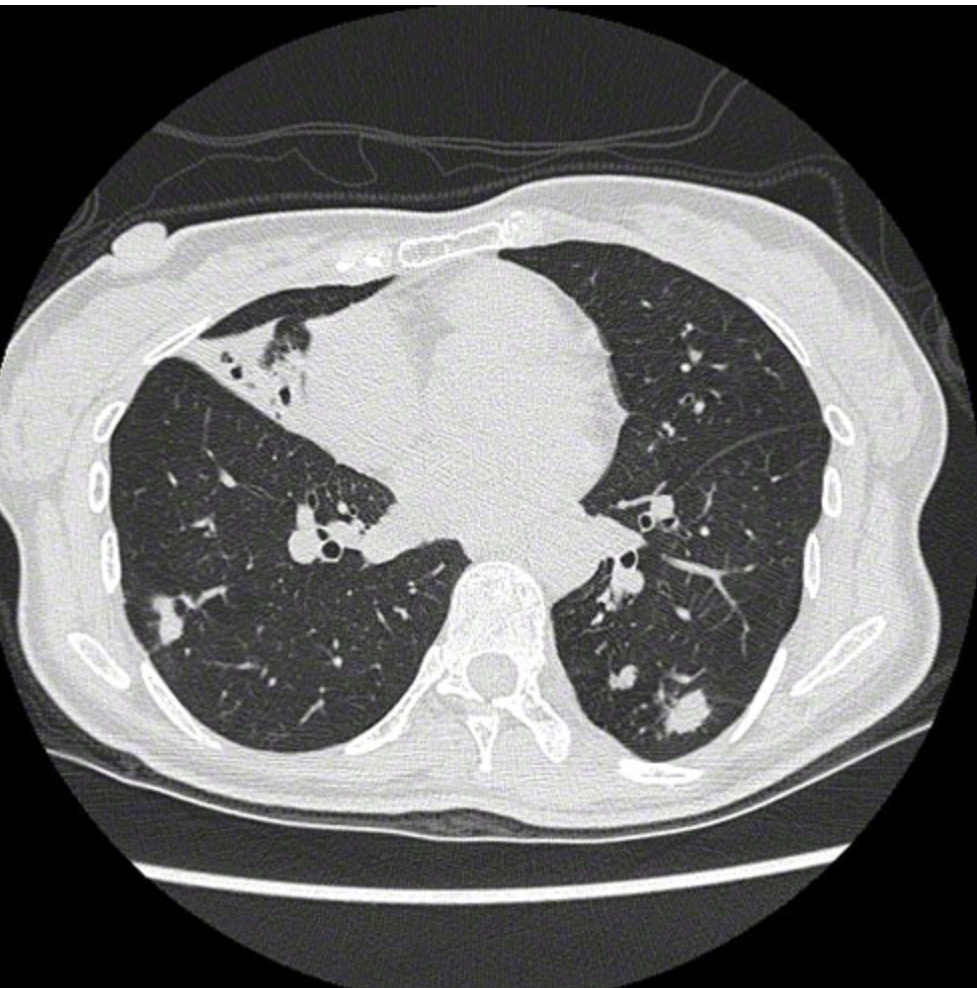

‘A 55-year-old woman comes to the office because of a 6-month history of cough productive of yellow sputum and a 1-week history of intermittent bloody streaks in her sputum. She also reports occasional night sweats during the past 3 months and an unintentional weight loss of 4.5 kg (10 lb) during the past year. She has not had fever, chills, chest pain, or shortness of breath. Medical history is notable for scoliosis and gastroesophageal reflux disease. Her only medication is omeprazole. She does not smoke cigarettes. She is 155 cm (5 ft 1 in) tall and weighs 40 kg (88 lb); BMI is 17 kg/m2. Temperature is 36.5°C (97.7°F), pulse is 102/min, respirations are 18/min, and blood pressure is 110/61 mm Hg. Pulse oximetry on room air shows an oxygen saturation of 98%. Auscultation of the lungs shows inspiratory crackles in the anterior right mid lung field. Musculoskeletal examination shows marked scoliosis. The remainder of the examination shows no abnormalities. X-ray of the chest shows multiple nodules in the left lower lobe. CT scan of the chest is shown. Which of the following is the most appropriate next step in management?